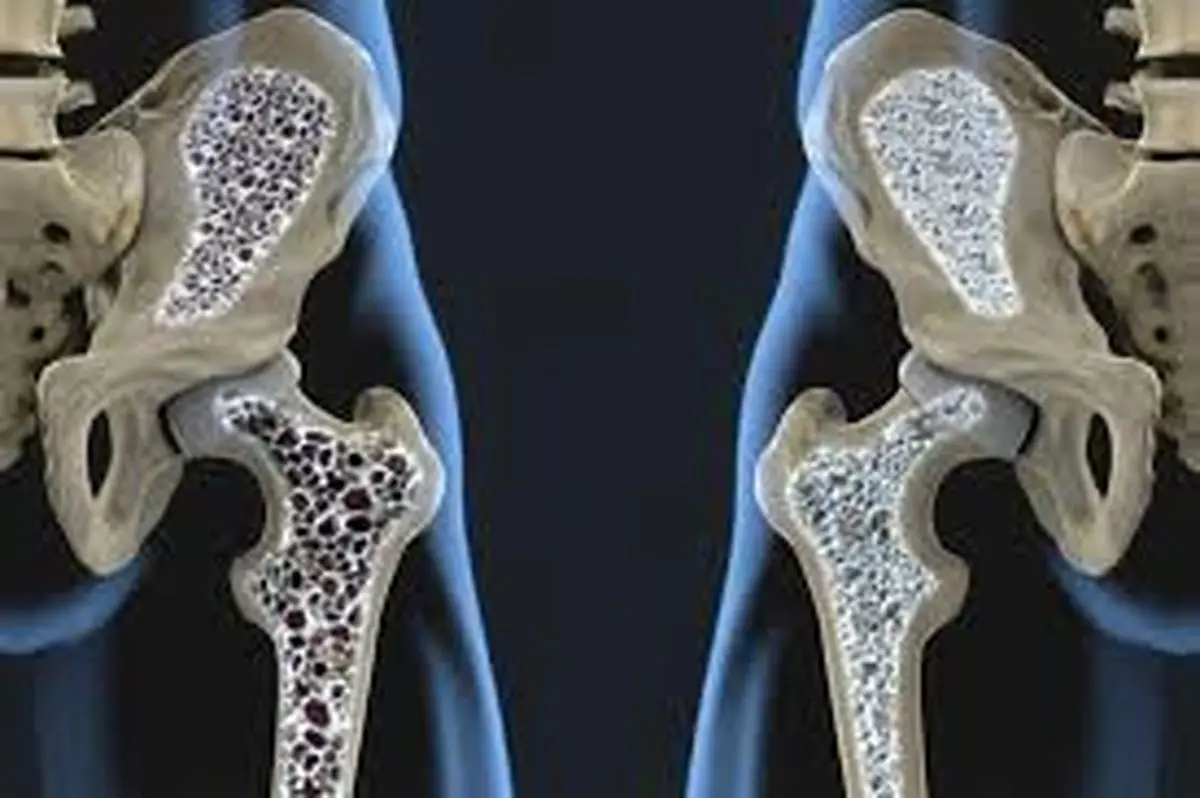

تفاوتهای پوکی و نرمی استخوان

پوکی استخوان یا استئوپروسیس (Osteoporosis) وابسته به سن و جنس و هورمونهاست که غالبا انتظار داریم بیشتر در خانمهای سالمند و بزرگسال بروز پیدا کند. اما نرمی استخوان که آن را با نام استئومالاسی (osteomalacia) میشناسند بیشتر در آقایان بروز میکند، البته برخی از خانمها هم به آن مبتلا میشوند، که عموما ناشی از کمبود املاح، کلسیم و روی است.

پوکی و نرمی استخوانها ازجمله عوارضی هستند که میتوانند در سنین بالا زنان و مردان را در زندگی دچار مشکل کنند. کلسیم در این میان نقش ویژهای در سلامت استخوانها دارد و کمبود آن میتواند به کاهش تراکم استخوانها و در نهایت پوکی استخوان در سالمندی منجر شود. اما تغذیه نقش زیادی در حفظ سلامت استخوانها دارد و رژیم غذایی اشتباه میتواند به سلامت استخوانها در درازمدت آسیب وارد کند. برای پی بردن به نقش تغذیه در حفظ سلامت استخوانها،گفتوگویی با دکتر منصور رضایی، متخصص تغذیه انجام دادهایم که در ادامه میخوانید.

تفاوتهای پوکی و نرمی استخوان

دکتر رضایی درباره ماهیت نرمی و پوکی استخوان و تفاوت این دو عارضه با یکدیگر، گفت: پوکی استخوان یا استئوپروسیس (Osteoporosis) وابسته به سن و جنس و هورمونهاست که غالبا انتظار داریم بیشتر در خانمهای سالمند و بزرگسال بروز پیدا کند. اما نرمی استخوان که آن را با نام استئومالاسی (osteomalacia) میشناسند بیشتر در آقایان بروز میکند، البته برخی از خانمها هم به آن مبتلا میشوند، که عموما ناشی از کمبود املاح، کلسیم و روی است.